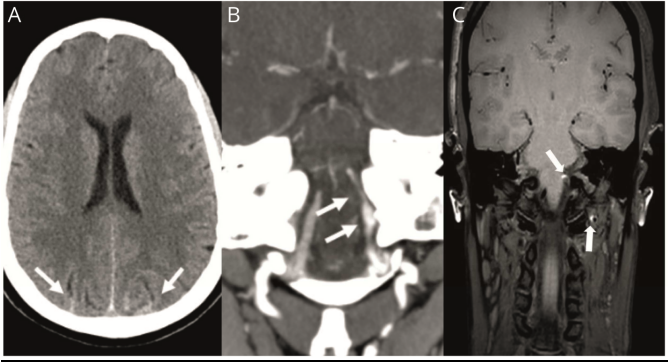

(SAH)(图1-A)。头颈部CTA显示右侧颅外以及左侧颅内和颅外椎动脉夹层,没有纤维肌发育异常的证据(图1-B)。该患者在产后第10天未再述颈部疼痛。左颅内椎动脉夹层导致动脉狭窄70%,其余颅内动脉正常。头颅MRI T1抑脂序列证实了夹层壁内血肿,并排除了脑梗塞(图1-C)。

图1 蛛网膜下腔出血和颈动脉夹层。

(A)轴位大脑CT平扫

显示双侧顶叶皮层蛛网膜下腔出血。(B)冠状位头颈部CTA显示硬膜内左椎动脉梭形扩张,随后变窄,与夹层一致;还可见双侧颅外椎动脉夹层(未显示)。(C)T1脂肪抑制显示壁内血肿。